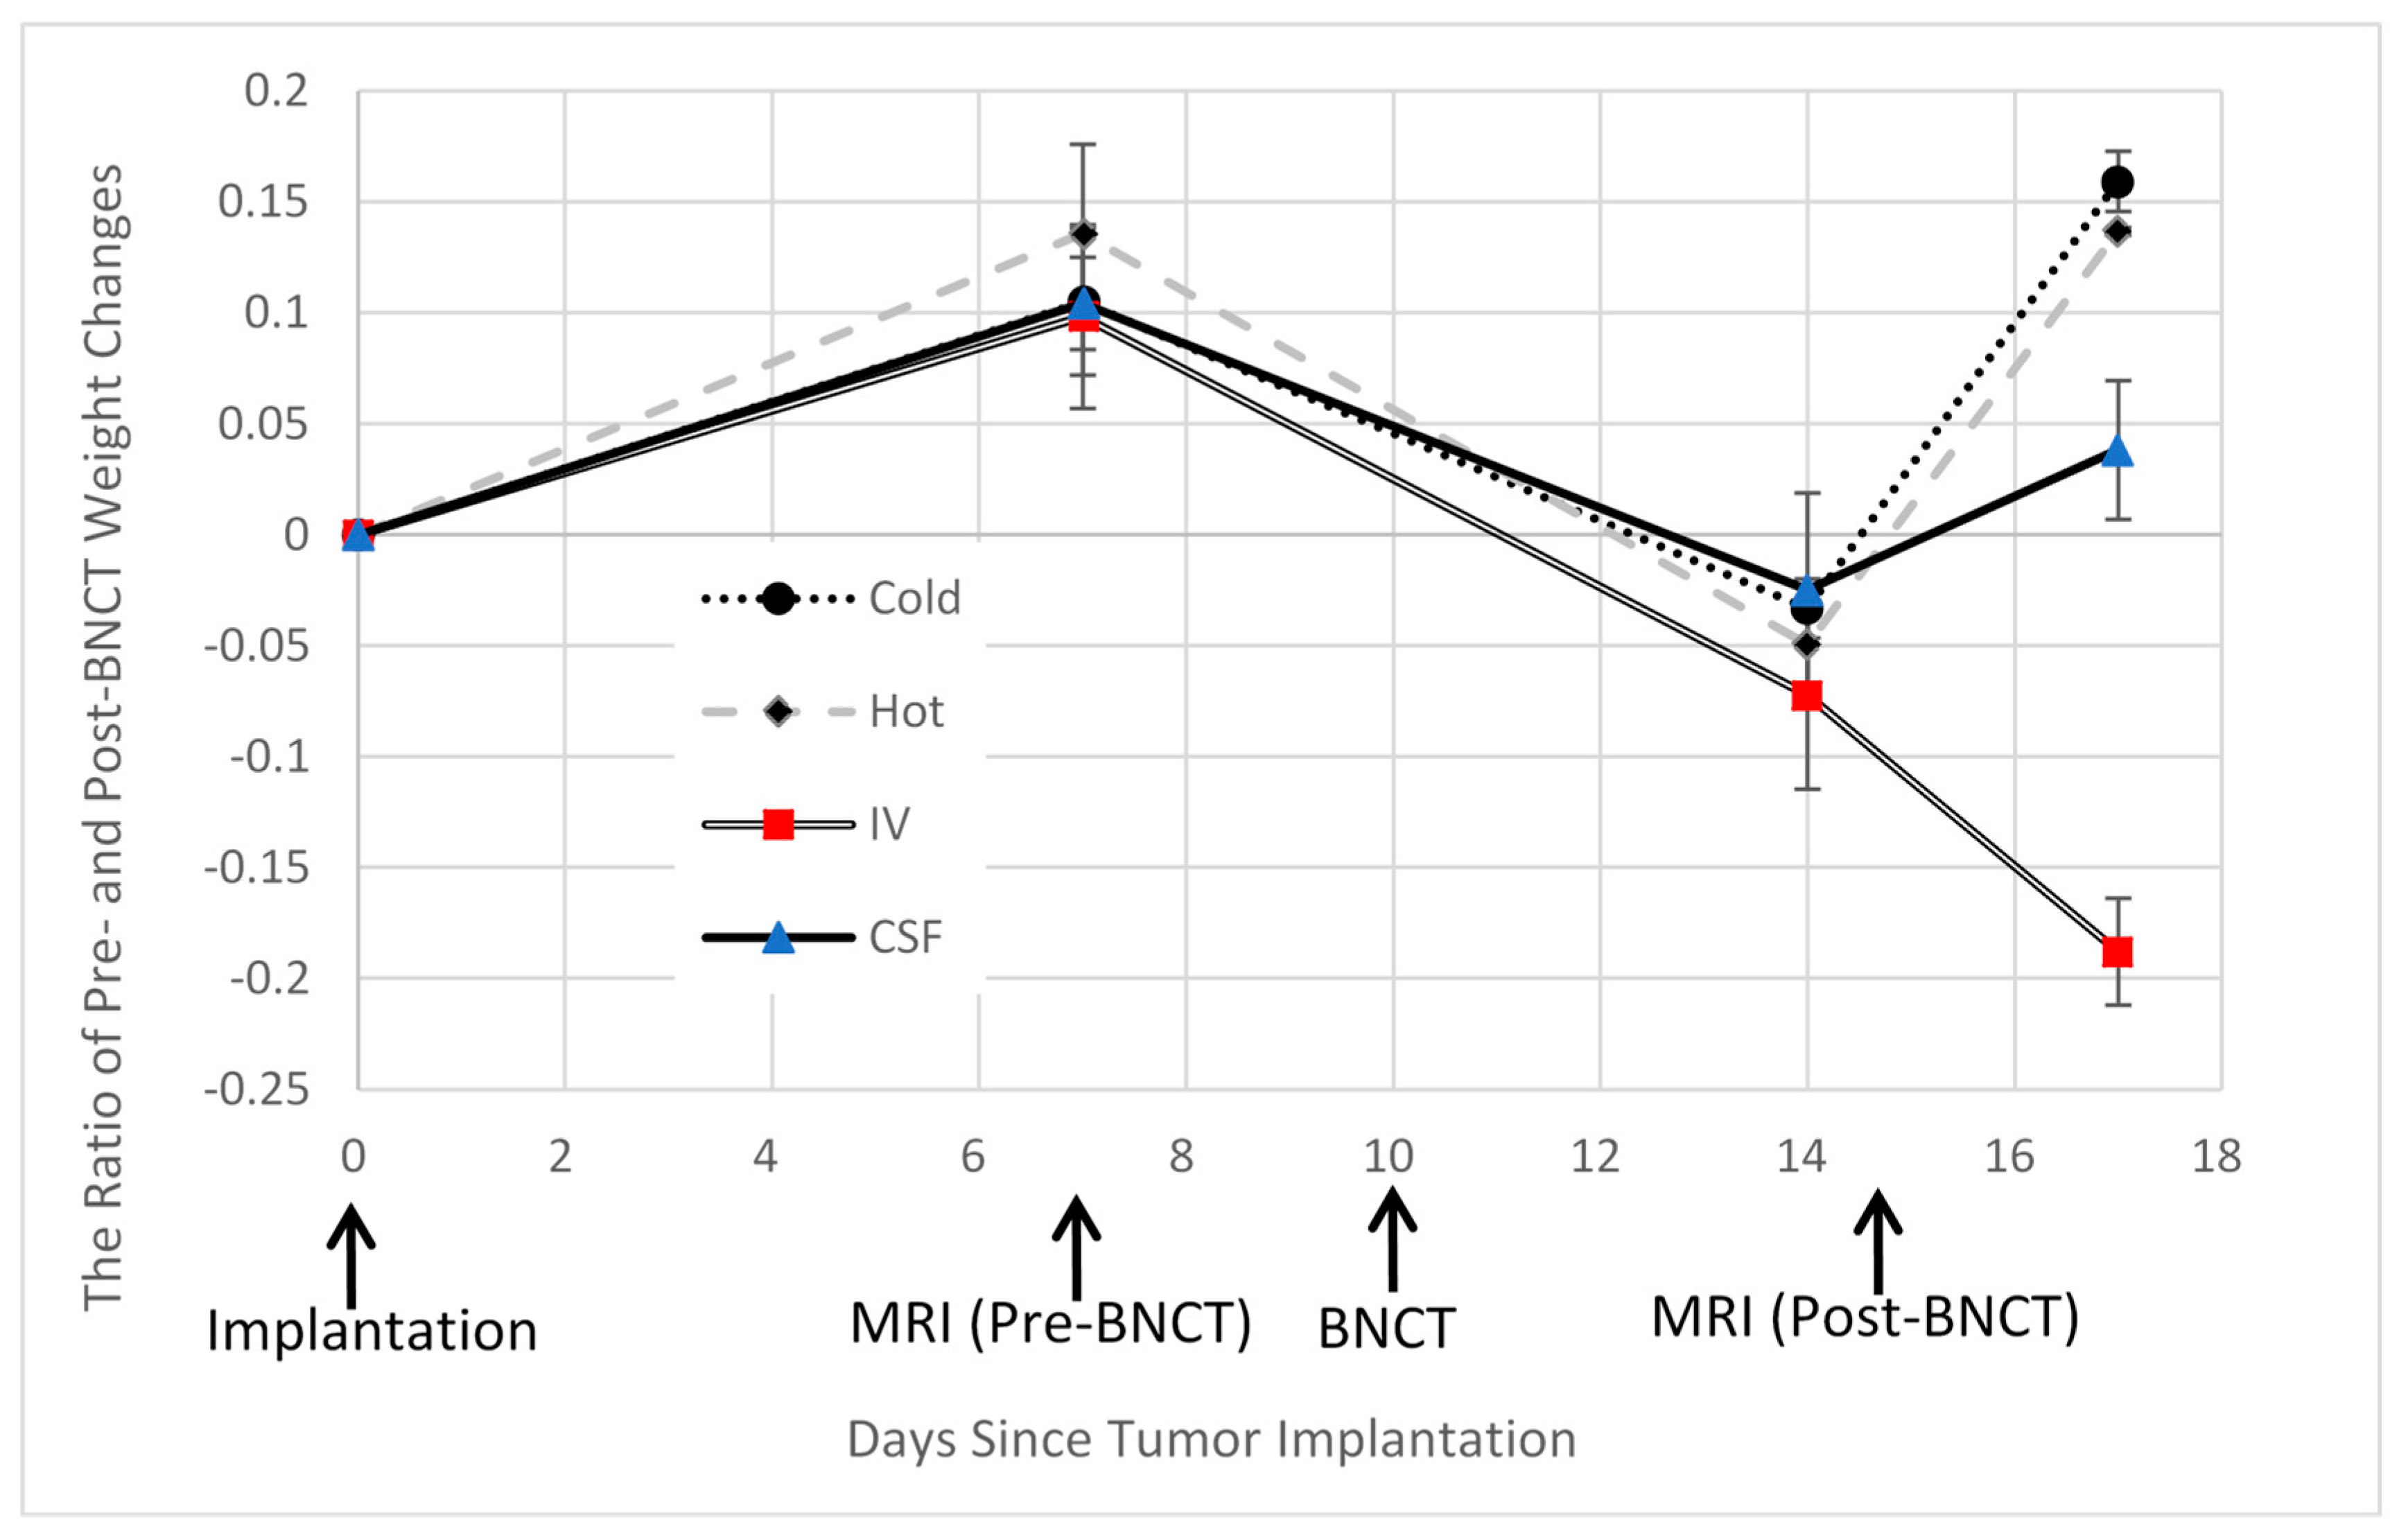

2.2. BNCT Effect on the CSF Administration Method of 10BPA

2.3. Pre- and Post-Treatment MRI Assessment

3. Results